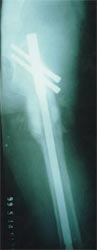

以上图片为三位患者的X线片,显示股骨粗隆下骨折、骨不连,内固定已经失败。

主要采用股骨重建髓内钉获得良好早期的稳定性,为骨愈合创造条件,